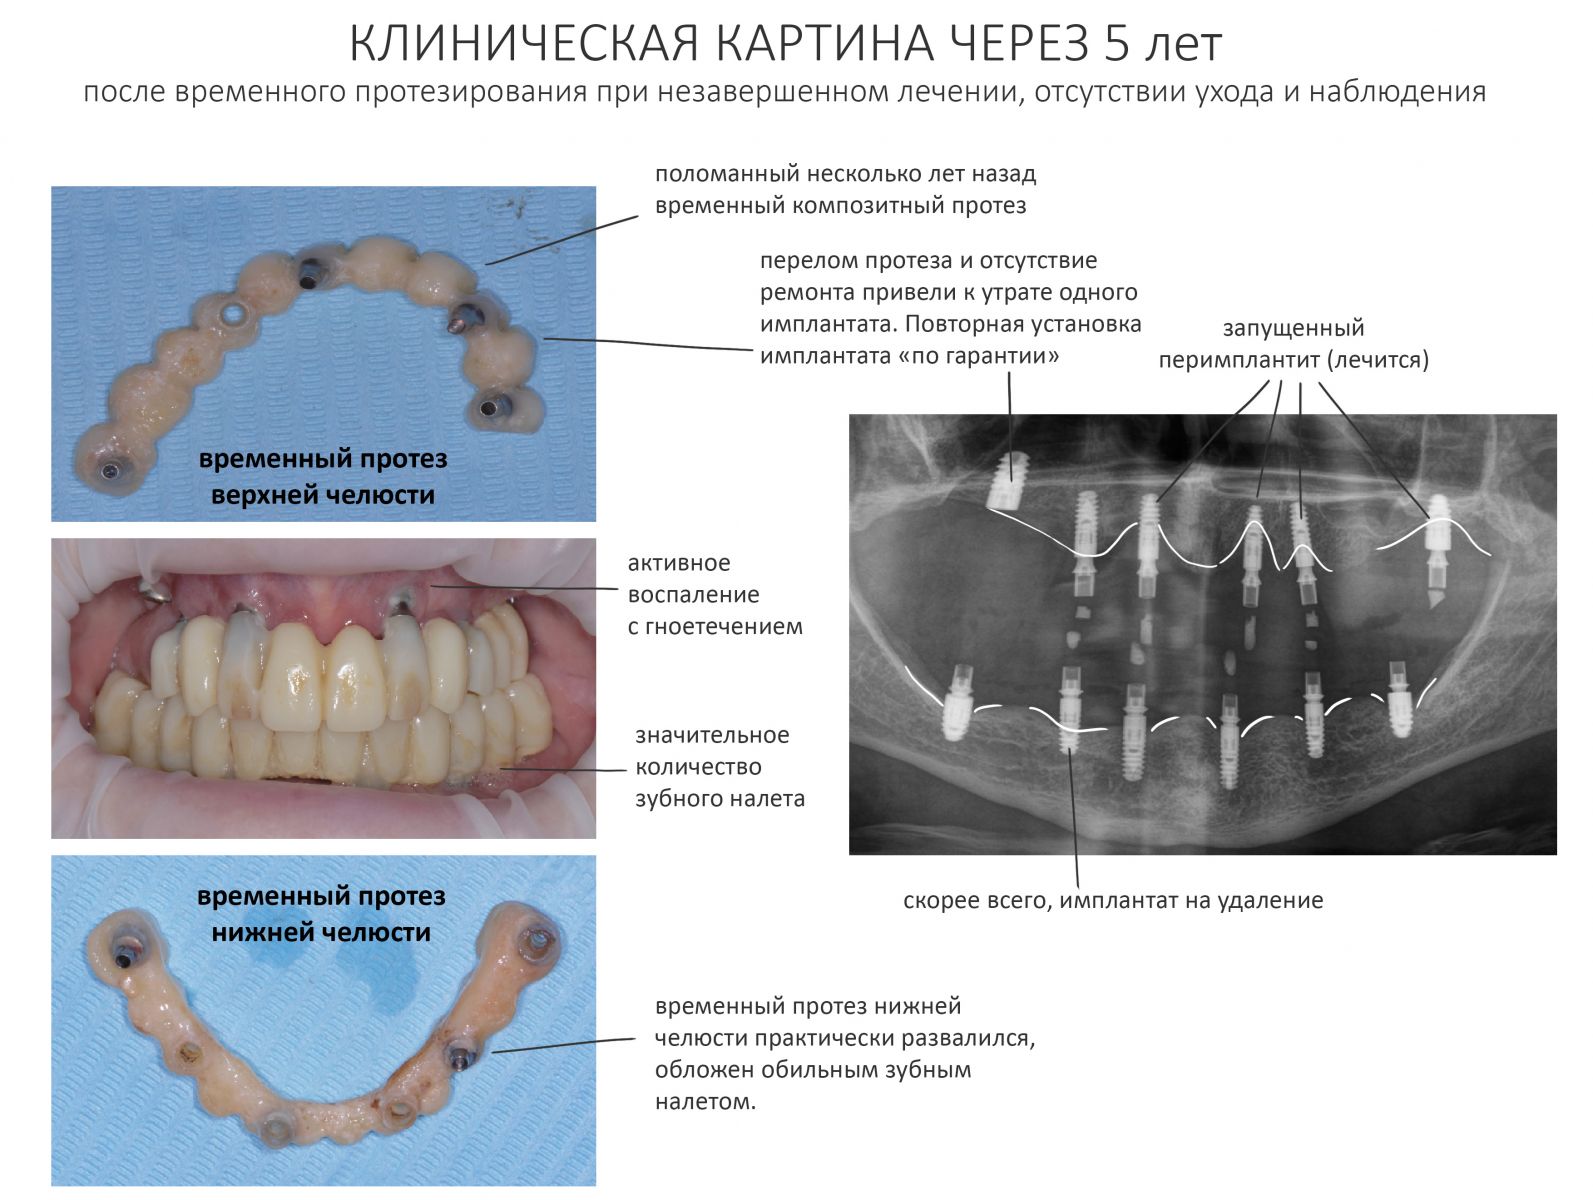

Прошло пять лет. Наконец, у Анны (так зовут неуловимую пациентку) появилось время. Но не на продолжение лечения, а для решения возникших стоматологических проблем, которых накопилось немало. Превысив все возможные и невозможные сроки службы временных композитных протезов (которые, кстати, стерлись в ноль, что привело к дисфункции височно-нижнечелюстного сустава), забыв про гигиену полости рта, она свела к нулю всё проведенное ранее лечение и довела установленные имплантаты до состояния, в котором их невозможно нормально протезировать: